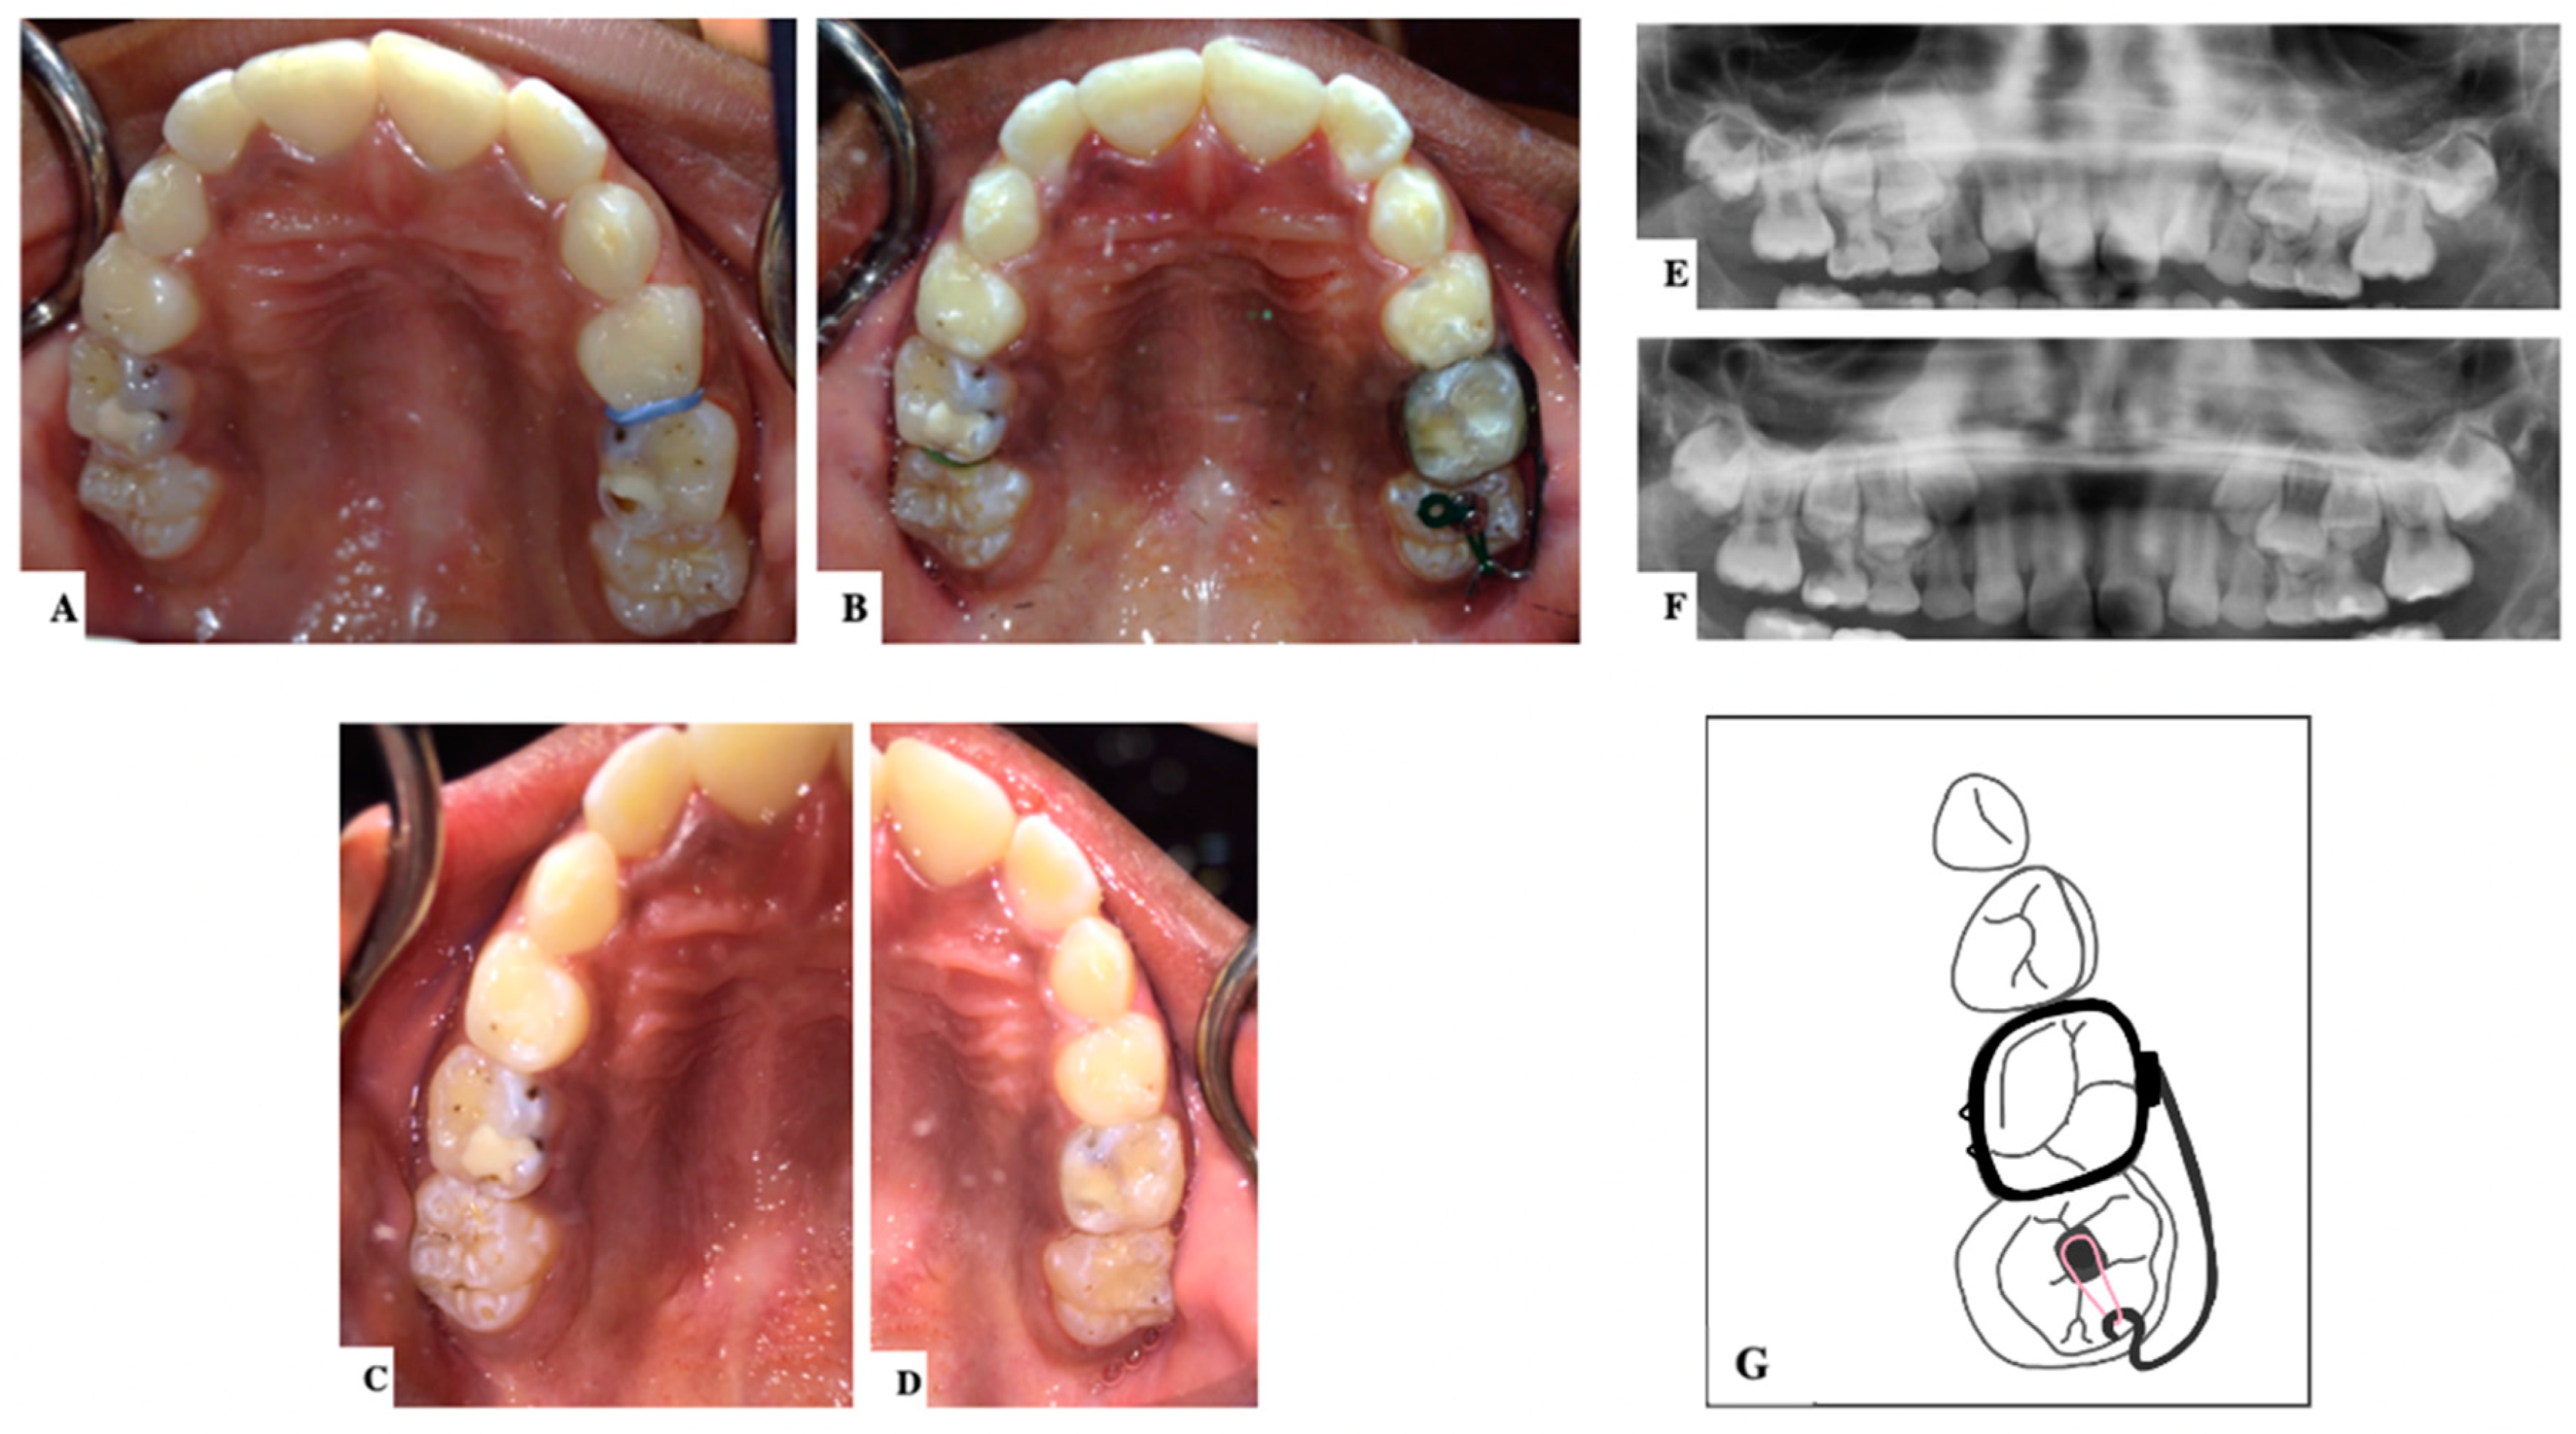

10. Ectopic Second Permanent Molars

11. Novel Devices

| Barberia-Leache ’s Classification (Based on the effect on second primary molar) * | |||||

| Grade 1 Mild | Grade 2 Moderate | Grade 3 Severe | Grade 4 Very severe | ||

| Limited resorption to the cementum or with minimum dentine penetration | Resorption of the dentine without pulp exposure | Resorption of the distal root leading to pulp exposure | Resorption that affects the mesial root of the second primary molar | ||

![]() | ![]() | ![]() | ![]() | ||

| Harrison and Michal’s Classification (based on severity of the lock using bitewing radiograph) * | |||||

| Normal | Minimal lock | Severe lock | |||

| No sign of impaction | Impacted less than half the width of the distal marginal ridge of the second primary molar | Impacted more than the width of the distal marginal ridge of the second primary molar | |||

![]() | ![]() | ![]() | |||